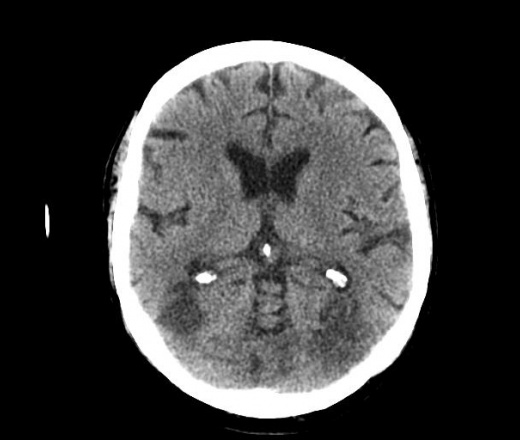

Уважаемые коллеги. Столкнулся с неоднозначной картиной при КТ головного мозга. Анамнез: мужчина с опухолью мочевого пузыря потерял сознание, сколько был без него - не знает, когда пришел в себя - "ослеп". Проведена КТ головного мозга с внутривенным "усилением". Чем могут быть, на ваш взгляд, обусловлены гиподенсивные зоны - метастазами или чем-то другим? Смущает, что нет типичного для метастаза феномена накопления контрастного вещества, да и вообще картина не характерная для них, на мой взгляд. Вот здесь http://files.mail.ru/67D10D5A26D74E27A6B5C2BFC12E9706 выложены две папки (нативное и с "усилением"), в которые упакованы изображения в формате dicom. Какие будут предположения? Благодарю за внимание. Нажимаем "читать далее"!

вторая из выложенных серий сделана непосредственно после окончания введения контрастного вещества (буквально через несколько секунд). Существует еще одна серия, сделанная через 10 мин. (по прошествии времени, необходимого для преодоления контрастным веществом гемато-энцефалического барьера), но там изменения идентичны второй, накопления контрастного вещества нет.

жаль что не весь объем вы выложили. по мне так похоже на mts. можно конечно предположить, что какой нибудь опухолевый тромб стрельнул в голову, произошла ишемия и развился ишемический инсульт, но не слишком похоже...

Как дилетант в кт отмечу, что в бассейны не вмещается инфаркт.

И смущает симметричность " метастазирования", это отек, но метастатический ли..